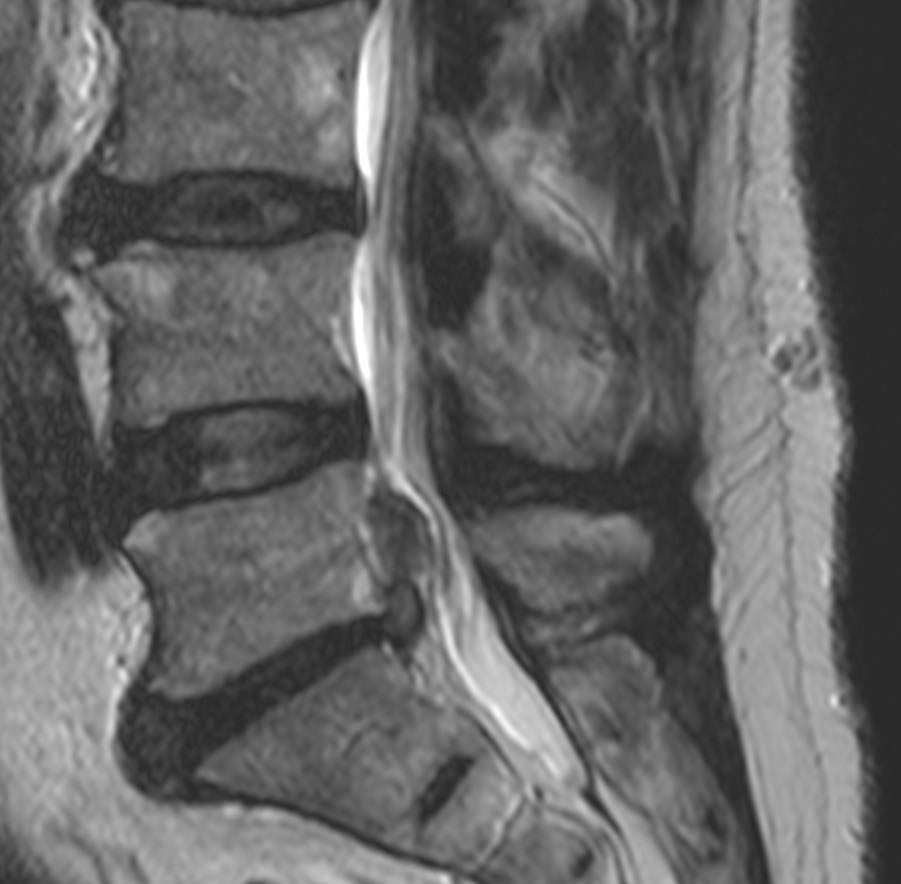

La hernie discale est une lésion provenant d'une dégénérescence d'une partie d'un disque intervertébral. En général, il y a une ouverture de l'anneau fibreux qui laisse sortir une partie du noyau pulpeux (mou) du disque intervertébral. Le fragment de disque mou s'échappe dans le canal rachidien et vient comprimer un nerf spinal. La compression et irritation du nerf provoque les douleurs de type "sciatique".

L'investigation principale est l'IRM de la colonne soit lombaire pour les hernies discales lombaire ou cervicale pour les hernies cervicales. Parfois il est utile de faire un éléctroneuromyogramme (ENMG) qui permet d'évaluer le degré d'atteinte de la conduction nerveuse.